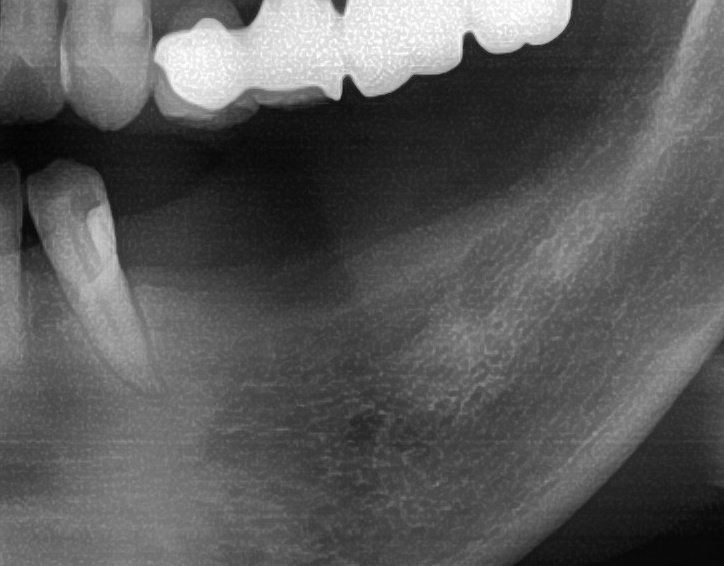

今回の患者様はインプラント植立を希望され、左下4番目・5番目・6番目の3本の植立が決まりました。

しっかりとインプラント埋め込まれた後は、動揺がないか、噛んだ時に当たらないかなどを確認して、最後にパノラマ写真を撮影して今回のオペは終了となりました。